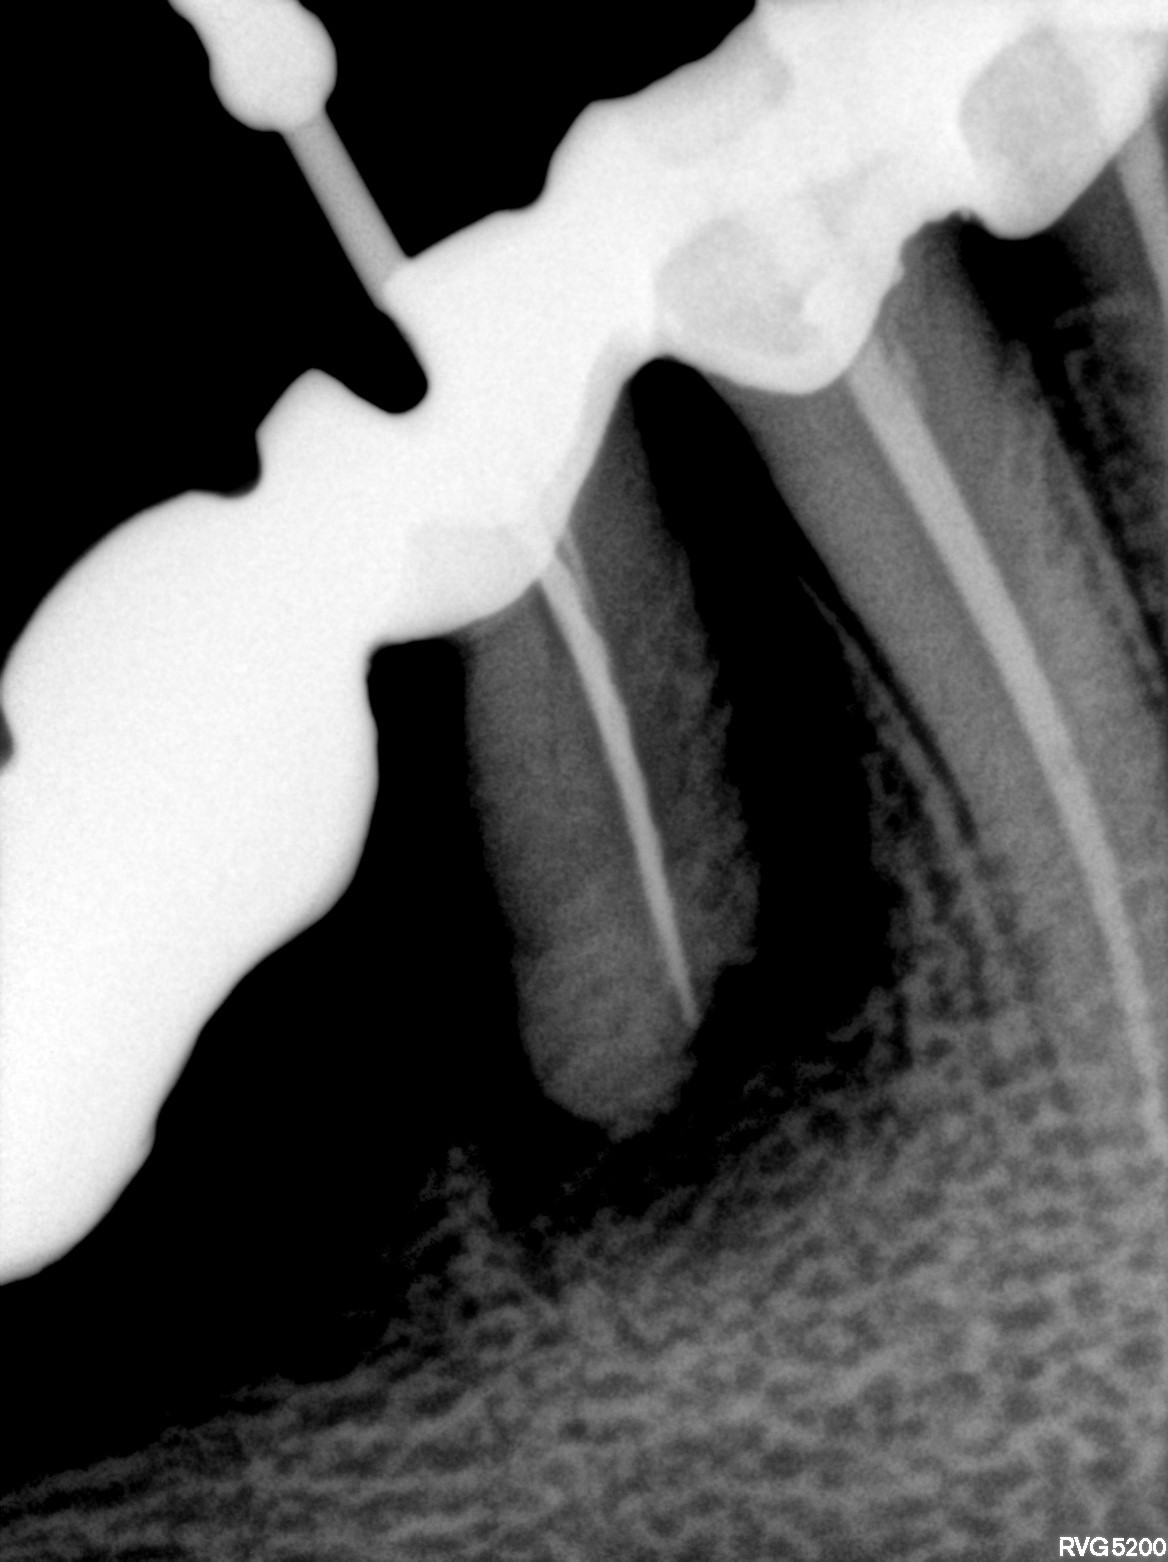

Dental Radiographs FHIR: DocumentReference · LOINC 24641-7

xray_1765005927_0.jpg

24641-7